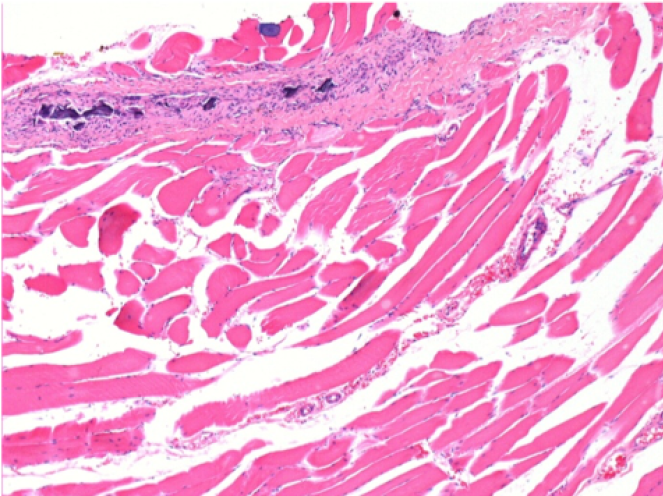

Iniezione Endopeel nel tessuto subcutaneo SC

0.5 ml ( 5x 0.1ml): Iniezione SC di Endopeel nel tessuto pretibiale subcutaneo SC destro (Dx).

Sx:200x-Controllo-SC

Dx-Giorno10-SC-200X

Dx-Giorno30-SC-200X

Dx-Giorno90-SC-200X

Dx-Giorno210-SC-200X

Dx-Giorno210-SC-400X

Endopeel induce una miofibrolisi selettiva reversibile e una risposta infiammatoria approssimativamente nel periodo di 1 mese.

I cambiamenti dei tessuti muscolari sono quasi completamente reversibili.

Il muscolo é il posto migliore per iniettare Endopeel ,per la sua maggiore efficacità, il controllo e la durata della sua azione.

Nessuna necrosi ne ascesso sono stati osservati durante la sperimentazione.